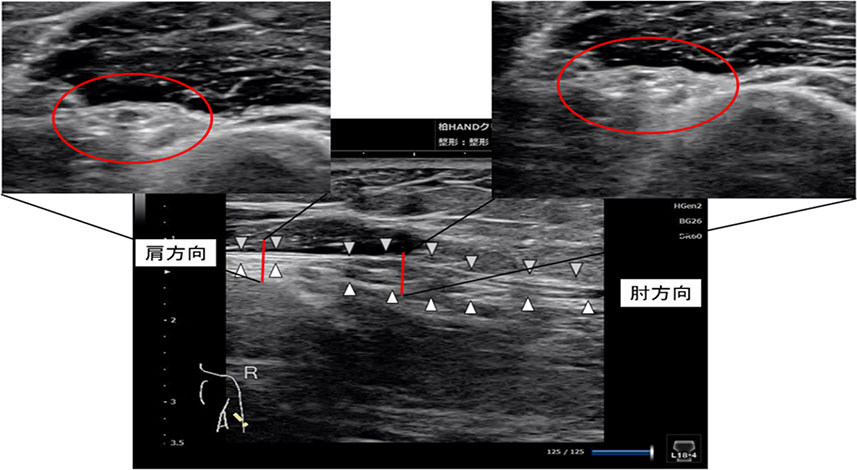

Q. どのような検査をしますか?

A. 各筋肉の筋力を測定する(徒手筋力テスト)と多くはわかります。

類似疾患との鑑別を有する際には、針を使った筋電図(神経支配されている筋肉の収縮の程度計測)をしますが、最近では超音波エコー画像で圧迫されて障害された神経の画像が描出可能です。

図は、腕の後ろの方で圧迫された障害された神経画像です。

(中央白△が神経の走行、中央が腫れている、横断面では損傷部の神経は腫れており、内部が不明瞭)